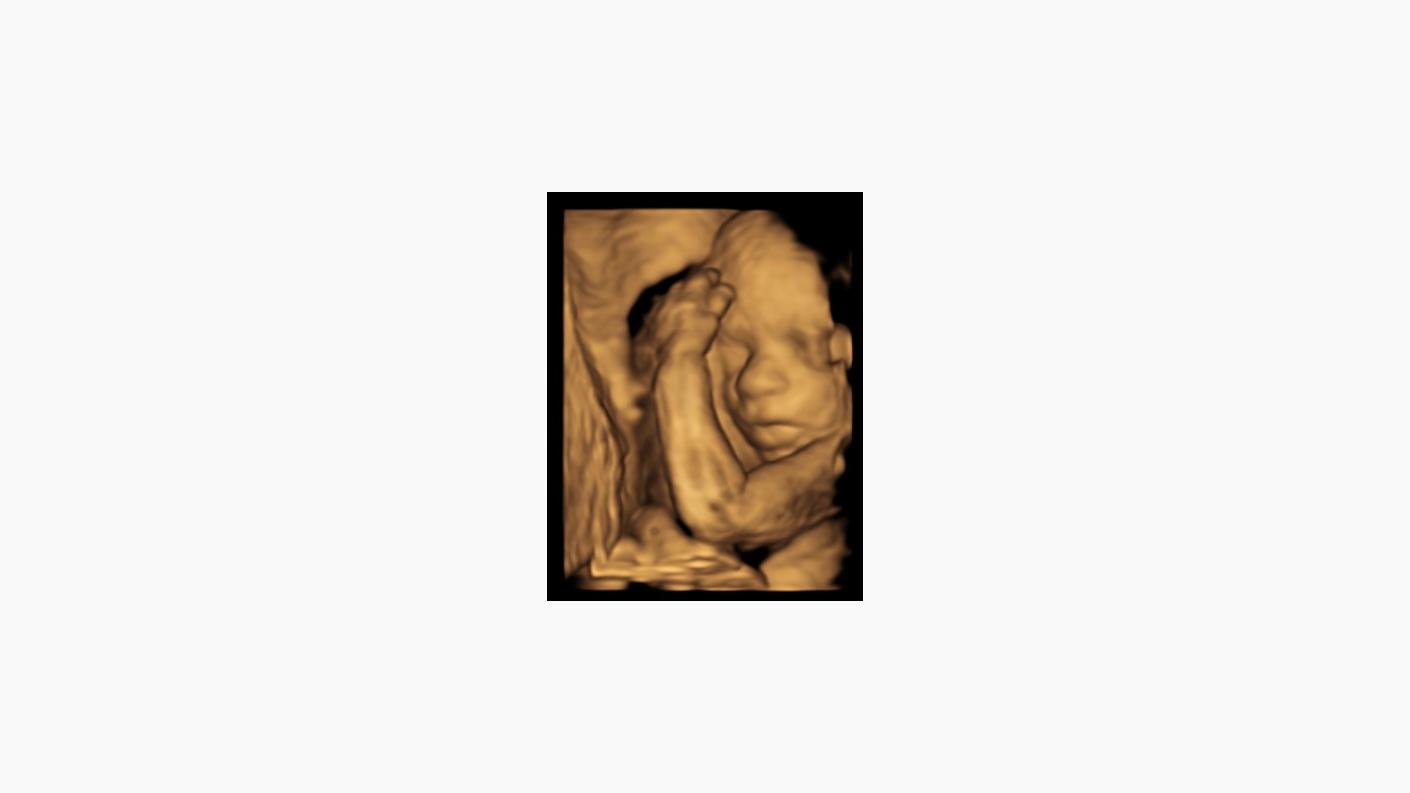

”Prin examenul morfologic de trimestrul II (ecografie de nivel II-B) se efectuează biometria fetală şi se vizualizează în detaliu anatomia fetală. Se notează localizarea placentei, anomaliile de cordon sau lichid amniotic. La acest moment se apreciază riscul de naştere prematură prin măsurarea lungimii colului uterin.

Ecografia fetală identifică doar malformațiile cu expresie imagistică la momentul examinării. Este posibilă uneori reexaminarea pacientei pentru completarea morfologiei dacă la examenul inițial fătul nu a stat într-o poziție favorabilă și nu au putut fi vizualizate detalii anatomice importante”.